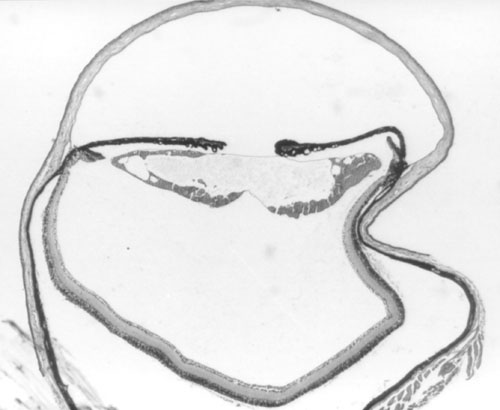

Figure 2. Histology of Ccw/+ eyes

A. Normal littermate 10 days post partum. B. Ccw/+ 10 days post partum. Some vacuolation of the lens is visible. C. Ccw/+ 20 days post partum. Lens fibers are becoming swollen and disorganized. D. Ccw/+ 4-6 weeks post partum. Lens fibers are largely degraded. E. Ccw/+ 14 weeks post partum. Only the lens capsule and some epithelium remain.